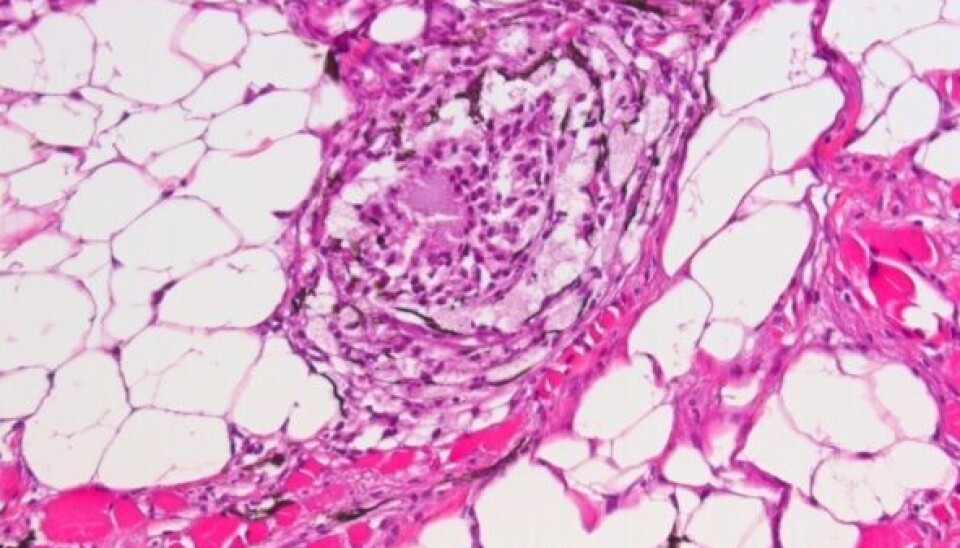

Los científicos noruegos identificaron el posible potencial que tienen ciertos biomarcadores plasmáticos de salmón del Atlántico para la detección temprana de la enfermedad del músculo esquelético y cardiaco (HSMI) causada por Piscine orthoreovirus-1 (PRV-1), esta patología es muy prevalente afectando la producción y el bienestar animal en los planteles productivos.

Por otro lado, durante la fase establecida de la enfermedad en la semana 8, las proteínas vinculadas al daño muscular y la activación inmunitaria (Creatina quinasa e histonas) se alteraron significativamente, lo cual se correlaciona con HSMI mencionaron los investigadores.